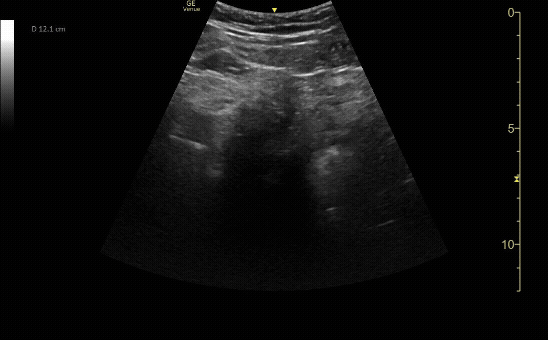

Sagittal view of the uterus with IUP and small subchorionic hemorrhage.

c/o Leslie Cachola MD